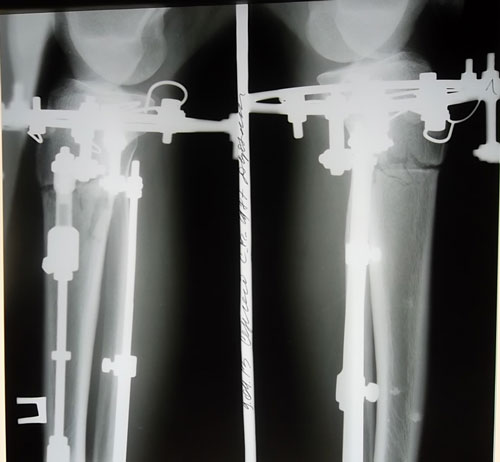

Всем здрасьти! меня зовут Сергей, я обладатель красивых кривых ноженек))) наверно вы все уже посмотрели)) совсем недавно а точнее в январе этого года я случайно набрал в яндексе (исправить ноги) и вот нарвалса на клинику Николая Николаевича..

Поглядите на мои ровные ножжжки)) я вообще доволен результатом!)) Спасибо Николаю Николаевичу!

Смотрю подмерзать стал-носочки одел. Палочки получились ровные. Теперь смело можешь вставать на ворота.